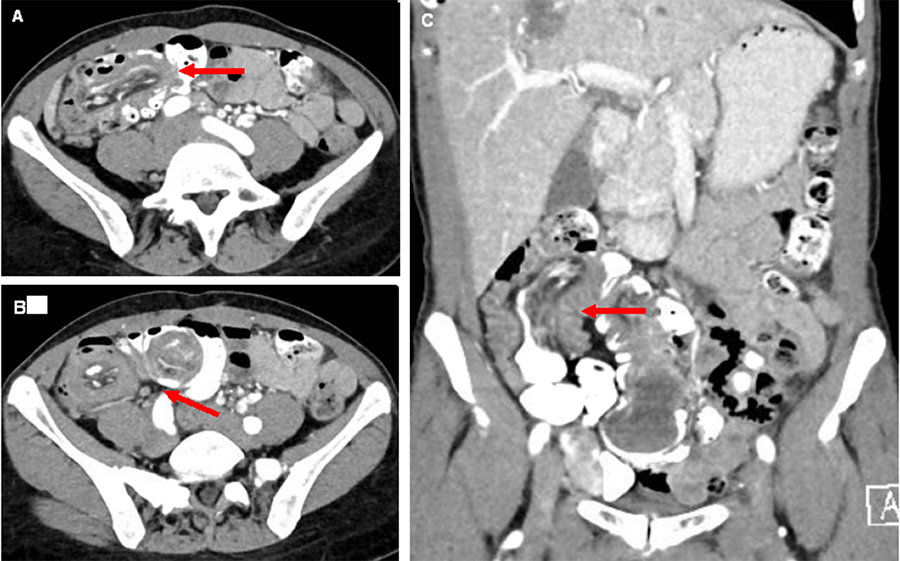

Approximately one year later, computed tomography (CT) of the abdomen and pelvis revealed long-segment ileocolic intussusception with a soft tissue mass at the distal end of the intussusceptum (Figure 1). Oral contrast passed the point of intussusception, and there was no proximal bowel dilatation. Due to this imaging finding, the patient was asked to present to the emergency department for an initial surgical evaluation.

Figure 1. Abdominal CT Imaging of Ileocolic Intussusception. Published with Permission

Representative axial views with A) long segment and B) classic “target sign” C) coronal view with long segment ileocolic intussusception. Red arrows highlight area of intussusception.